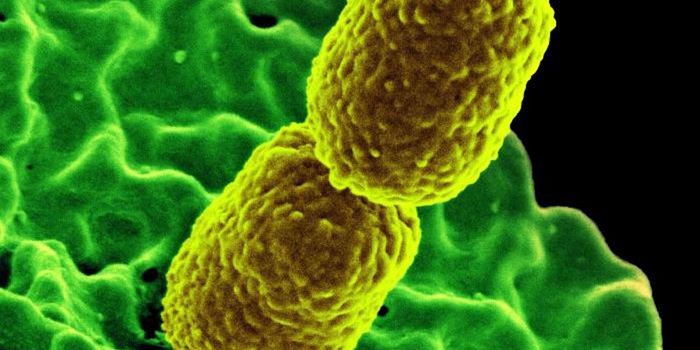

MAR 09, 2022MicrobiologyAntibiotic resistance is already a major threat to public health; in 2019 alone, antibiotic resistant bacterial infectio ...